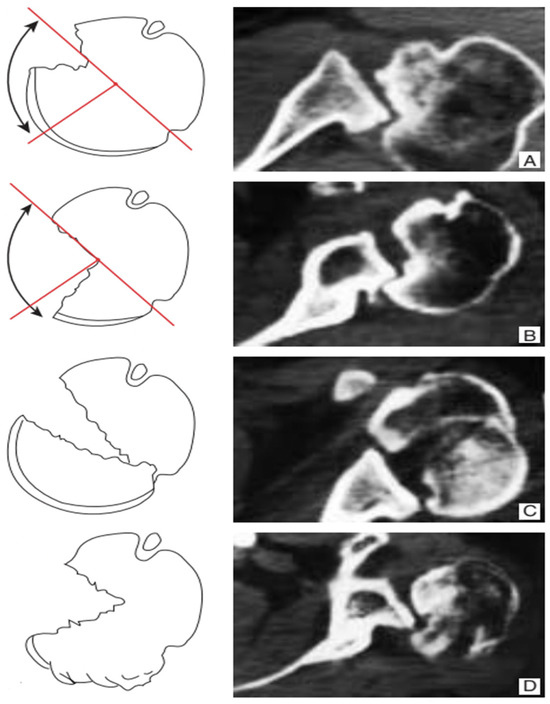

• Bone Grafting (Randelli Type 1): For Type 1 lesions with repairable impact injuries, particularly in younger patients and within a few weeks of trauma, bone grafting was performed. This involved detaching the subscapularis tendon, elevating the articular surface, and filling the defect. Bone grafting was specifically employed in cases classified as Randelli Type 1, characterized by a bone loss ranging from 20% to 50% of the humeral head articular surface. In all such instances, femoral head allografts sourced from a tissue bank were utilized. These allografts underwent precise intraoperative shaping to achieve an accurate press-fit within the humeral head defect. Fixation was then achieved using cannulated screws with washers, carefully positioned to ensure the screw heads were completely recessed and flush with the articular surface, thereby preventing any impingement. The rationale for selecting large, structural allografts from a tissue bank was based on the substantial dimensions and specific anatomical contouring required for effective reconstruction of these defects. Our unit benefits from a consistent supply of bone tissues, updated monthly through a collaboration with the Musculoskeletal Tissue Bank (BTM) of Bologna (Rizzoli Hospital), which ensured the ready availability of appropriate allografts for these procedures. The subscapularis tendon was then re-fixed in its original position with transosseous sutures (as illustrated in Figure 2 and Figure 3). The choice between synthetic grafts, cancellous allografts, or structural femoral-head allografts was based on lesion size and the quality of the residual humeral head bone stock.

• Subscapularis Transposition (McLaughlin Technique) (Randelli Type 1): In Type 1 lesions where the impact injury was not deemed repairable due to chronicity (e.g., 6–8 weeks post-trauma), the subscapularis tendon was transposed into the defect and fixed with transosseous sutures or anchors (as illustrated in Figure 4).

In the 2 patients with repairable type 1 impact injury, in consideration of the time elapsed since the trauma of 3 weeks and their young age, the subscapularis tendon was first detached, then the articular surface was raised, filling the defect with cancellous allograft bone in 1 case and with synthetic bone in the other. Finally, the subscapularis tendon was fixed with transosseous suture in the original position (Figure 2).

In the other 2 patients in whom the impact injury was not repairable due to chronicity (6–8 weeks from the initial trauma), only the subscapularis tendon was transposed inside the injury and fixed transosseous sutures in 1 case and with 2 anchors in the other case (Figure 4).

The remaining 2 patients with type 1 injury 4 weeks after the trauma were treated by detachment of the subscapularis tendon, debridement of the humeral bone bed and the defect was filled with a structural wedge-shaped femoral head allograft fixed with 2 cannulated screws slightly sunk into the articular surface. Subsequently the tendon was sutured back to its original insertion (Figure 3).

Figure 2. A 28-year-old man diagnosed with type 1 injury 3 weeks after the trauma treated with reduction in the dislocation, detachment of the subscapularis, reduction in the articular surface, bore with spongy bank bone and suture in anatomical position with transosseous stitches of the tendon.

Figure 4. A 47-year-old man with type 1 injury 6 weeks after trauma; we proceeded with reduction in the dislocation, bleeding of the bottom of the lesion and transposition of the subscapularis tendon anchored to the bottom with transosseous stitches.